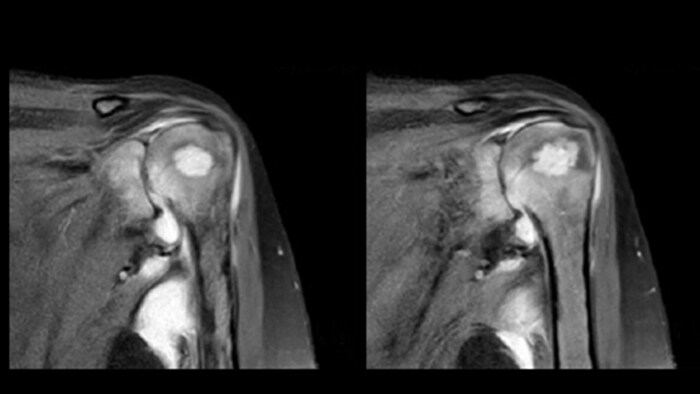

In these MRI images a focal lesion can be seen in the left humoral head with erosion of cortex. Multiloculated collection around the shoulder joint effusion, synovial thickening, and reduced joint space for arthritis were also suggested. The findings are compatible with infective etiology.